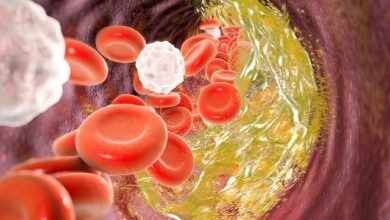

खतरे की घंटी! सारी बीमारियों की जड़ गाढ़ा खून, पतला करने के बेस्ट देसी नुस्खे

डेस्कः खून गाढ़ा मतलब शरीर बन रहा बीमारियों का घर, आपने बहुत से लोगों के मुंह से कहते सुना होगा कि…